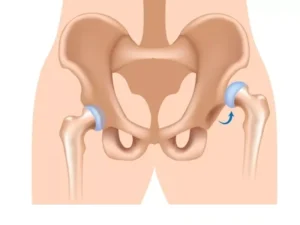

مراقبت های بعد از تعویض مفصل لگن بخش حیاتی از

تعویض مفصل لگن یک روش جراحی است که در آن